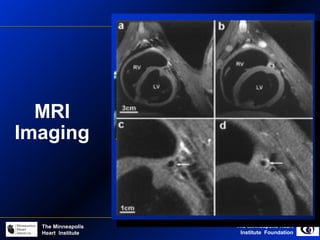

MRI

Imaging

Self-contained

portable MRI

catheter

Catheter Based MRI Imaging

Ex-vivo MR imaging: human coronary arteries

Adaptive intimal

thickening

LAD atheroma

Observation:

Significant technical

developments are needed

for MRI. Problems of

Spatial and Temporal

Resolution, and Acquistion

remain a major

impediment to clinical

coronary imaging in living

patients.